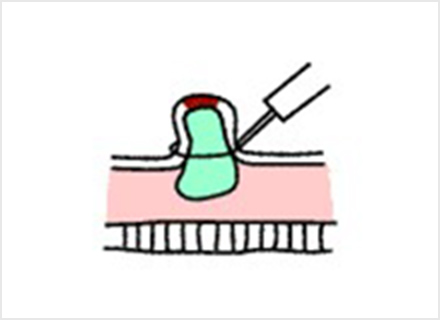

内視鏡的粘膜切除術:EMR(Endoscopic mucosal resection)

スネアと呼ばれる金属の輪を病変部に引っ掛け、高周波電流を流して病変を切り取ります。EMRは、治療が比較的短時間ですみますが、一度に切り取ることができる病変の大きさは、スネアの大きさ(約2cm)までと制限があります。

内視鏡的粘膜下層剥離術:ESD(Endoscopic submucosal dissection)

専用の処置具を使いより広範囲に病変を切り取ることが可能な治療法です。切り取られた病変は、最終的に顕微鏡でその組織の様子が確認されます(病理検査)。この方法では、大きな病変をひとかたまりで取り、病理検査でより正確な診断を行うことができます。

ESDは大きな病変も一括して切除可能ですが、手技が煩雑で時間がかかり、出血や穿孔などの併発症が生じる場合があります。ほとんどの場合内視鏡的に止血可能ですが、稀には輸血、開腹手術などを要することがあります。